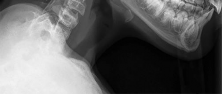

A 25-year-old male is involved in a high-speed motor vehicle collision. Radiographs demonstrate a traumatic spondylolisthesis of the axis (Hangman's fracture) with an oblique fracture line through the pars interarticularis, minimal translation, but extreme angulation (>11 degrees). The C2-C3 disc space appears disrupted posteriorly. According to the Levine-Edwards classification, what is the most appropriate initial management for this specific injury pattern (Type IIa)?

The scenario describes a Levine-Edwards Type IIa Hangman's fracture. This injury is caused by a flexion-distraction mechanism, leading to severe angulation with minimal initial translation. A critical point in management is that axial traction is STRICTLY CONTRAINDICATED, as it will exacerbate the distraction and worsen the deformity. The appropriate non-operative management involves the application of a halo vest under gentle compression and extension to reduce the angulation and stabilize the fracture.